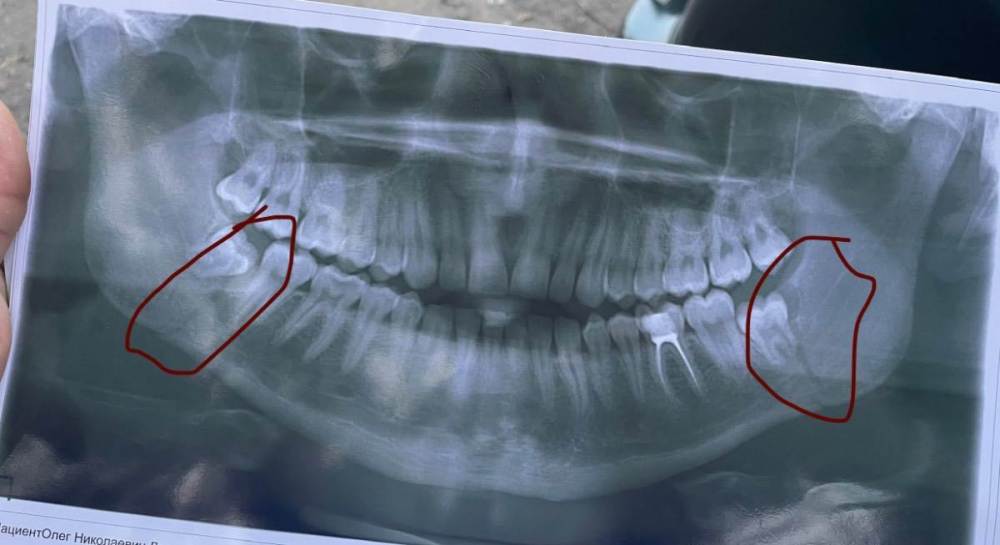

NightFox23 Опубликовано 27 августа, 2022 Поделиться Опубликовано 27 августа, 2022 Доброго времени суток ,помогите пожалуйста с решением моей проблемы У меня двусторонний перелом (парень 23года) без смешения и без осколков ,в ночь перелома обратился в травмпункт ,но там посоветовали утром сделать снимок и потом к ним вернуться .На следующий день вернулся к ним же со снимком ,сказали 2 варианта лечения ,повязка или шины ,по началу забоялся ставить шины ,думал ну не дурной и с повязкой справлюсь ,но спустя два дня понял ,что моя челюсть без моего ведома «убегает» и не сходит отёк с лица ,после этого я опять вернулся к тем же врачам для установки шин ,шины установили и сделали контрольный снимок сразу же ,сказали что все отлично встало Так вот ,у меня такой вопрос ,перелом был в ночь с 5-6 августа ,шины установили 8 августа ,на момент моего сообщения 27 августа ,теперь сам вопрос ,сегодня я снял резинки ,потому что уже верхние зубы очень сильно болят и челюсть по ночам «дергается»,от этого каждое утро ,боль в ушах ,скажите пожалуйста (болей в месте перелома не ощущаю) до этого соблюдал все рекомендации врачей ,теперь все таки сам вопрос ,насколько критично что я снял резинки и могу ли я снять шины раньше чем 8 сентября ? зубы никакие не удаляли ,так как сказал врач ,что они хоть и в области переломов ,но они не мешают сращиванию Ссылка на комментарий

Женька Опубликовано 27 августа, 2022 Поделиться Опубликовано 27 августа, 2022 Здравствуйте. Вы в трампункте были или в ЧЛХ отделении? Снимок до наложения шин. По это снимку я бы убрал Ваши обе восьмёрки в момент наложения шин, а дальше снимок и определение необходимости операции. Тк на мой взгляд зубы именно непосредственно в линиях переломов. Скиньте либо КТ свежее, либо хотя бы такой же снимок после снятия тяг. Резинки то меняли Вам? Ссылка на комментарий

NightFox23 Опубликовано 27 августа, 2022 Автор Поделиться Опубликовано 27 августа, 2022 (изменено) Обращался в ЧЛХ ,снимок сделан до наложения шин ,врач ,хирург ,сказал что зубы не мешают при срастании ,КС у меня на руках нет ,он остался в больнице ,а сам вот ещё не делал ,завтра заеду сделаю ,просто в нашем городе ,почему-то оказалась огромная проблема найти хирурга ,который бы ответил на мой вопрос ,а в ту больницу ,в которой накладывали шины ,сказали «чтобы больше к нам не приезжал» (не прям дословно ,но смысл этот забыл ответить про резинки ,да ,один раз приехал в областную ,они поменяли ,но знаете ,как-то скрипя зубами ,потом ещё и спросили ,а почему я приехал к ним,а не к другим ,а вторую замену ,я уже сам делал ,так как хамского отношения к себе не хочу ,тем более я это делал «профессиональнее» чем врач Изменено 27 августа, 2022 пользователем NightFox23 Ссылка на комментарий